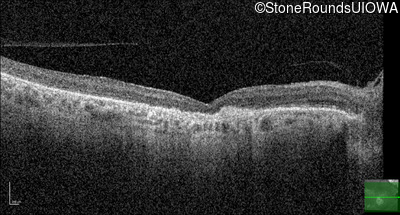

Infrared Fundus Photograph - Left - 20/100

Exemplar